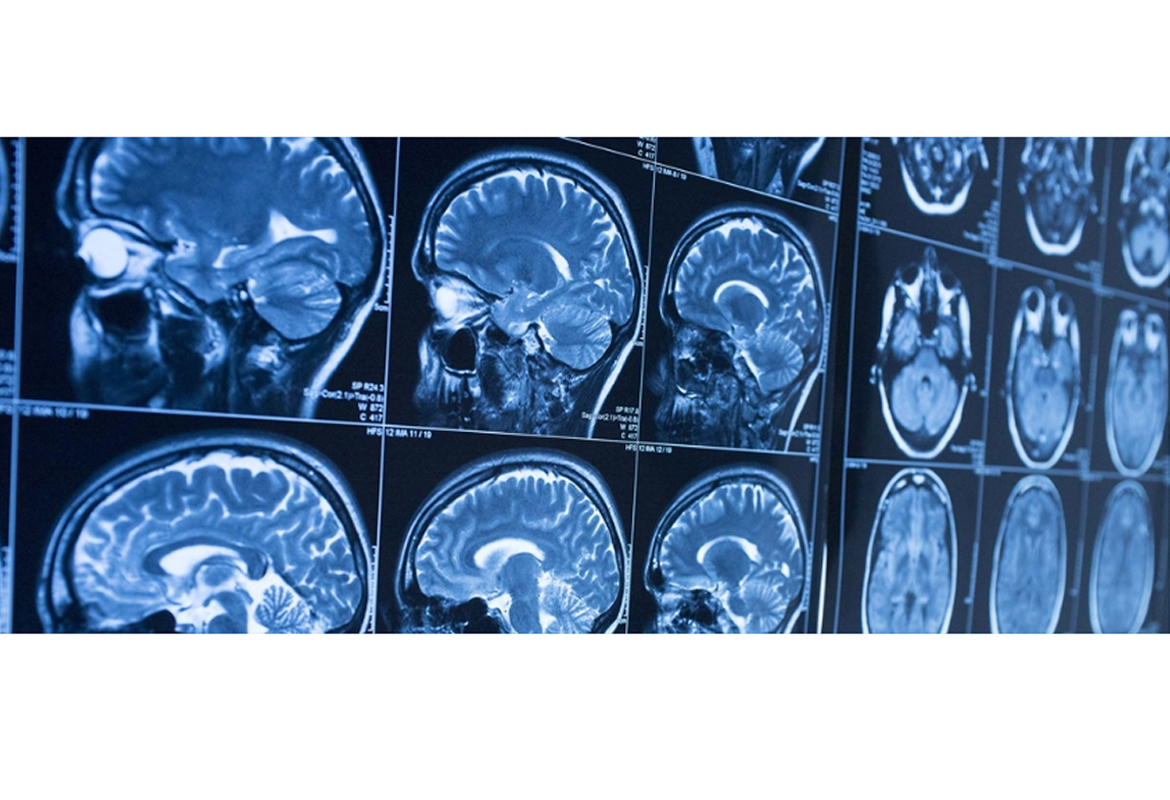

New global brain consortium at the Ludmer Centre for Neuroinformatics & Mental Health

A new $10-million investment from the Ludmer Family Foundation will establish the Ludmer Centre Heritage Fund and help launch and support a Global Brain Consortium of leading brain research institutions focused on sharing infrastructure, methodologies and results, ultimately accelerating treatment for patients.